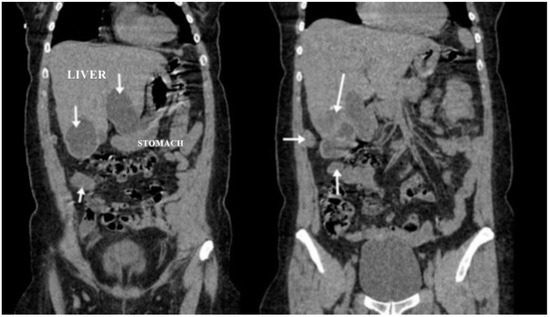

A CT examination revealed multiple cystic images in the hepatic segments V, VI, and VII, with subhepatic extension and involvement at the fissures of the venous ligament. Cystic images were also observed in the anterior abdominal wall and submesocolic (Figure 5, Figure 6, Figure 7, Figure 8 and Figure 9). Blood tests showed no significant abnormalities, and ELISA determination of IgG class antibodies to Echinococcus granulosus was positive at 1.66 IV (with values considered negative at ≤0.9 IV and positive at ≥1.1 IV).

The imaging highlights hepatic cysts in segments V, VI, and VII, a large cystic formation in the round ligament, a cyst in the parietal peritoneum, two cysts in the greater omentum, and two cysts located in the submesocolic enteral mesentery.

Figure 7. Coronal section (liver, round ligament, mesenteric, omental, and peritoneal hydatid cysts indicated by arrows).